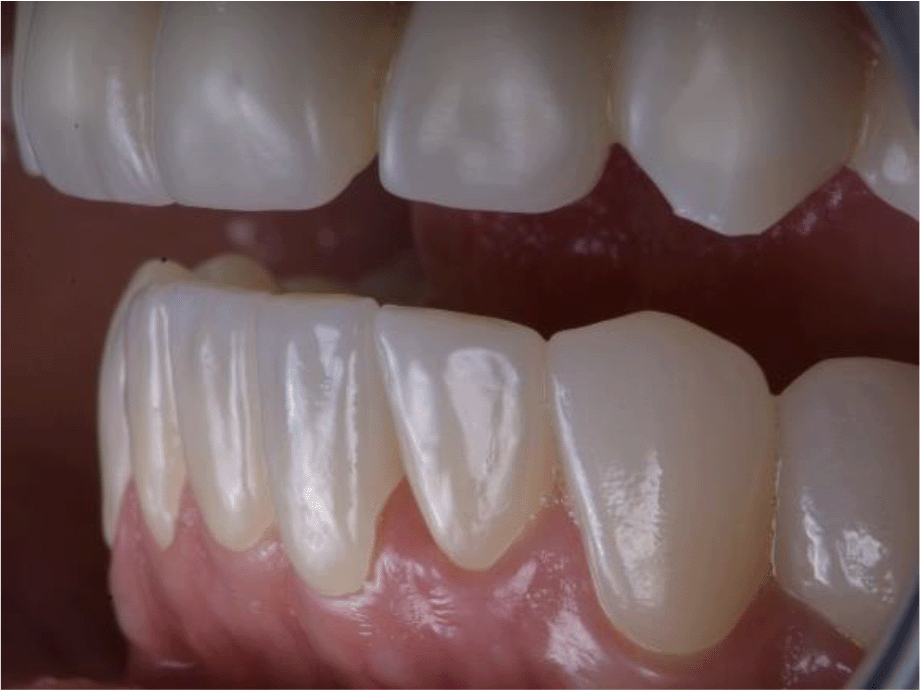

The patient reported a lack of symptoms of TMJ after 3 months, establishing the therapeutic effect of the splint. We then proceeded to the final prosthesis. All constructions were made of ceramics based on zirconium dioxide, with added yttrium and hafnium oxides. The distal defects of the lower jaw were solved with bridge constructions, and single crowns were placed on the frontal teeth (Figures 19 and 20).

All of the final constructions were made from Ceramill Zolid FX MultiLayer B2 and Glase (AmannGirrbach). For the upper jaw, single zirconia crowns of the canines and block crowns of 11, 12 and 21, 22, respectively, were made, for the distal defects - bridge restorations of zirconia ceramics. The distal structures of both jaws were cemented first to ensure stable occlusion. Then the crowns were fixed almost at the same time in the frontal section (Figures 21 and 22).

26dd931c-41d3-478d-bec1-8cb211d0a4b8_figure21.gif

Figure 21. Lower zirconia crowns, upper PMMA during the try-in procedure.

26dd931c-41d3-478d-bec1-8cb211d0a4b8_figure22.gif

Figure 22. Upper and lower zirconia crowns.